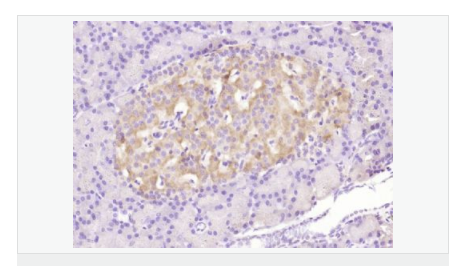

| 產(chǎn)品應(yīng)用 | WB=1:500-2000 ELISA=1:5000-10000 IHC-P=1:100-500 Flow-Cyt=3μg /test (石蠟切片需做抗原修復(fù)) not yet tested in other applications. optimal dilutions/concentrations should be determined by the end user. |

| 免 疫 原 | KLH conjugated Synthesised phosphopeptide derived from human Bax around the phosphorylation site of Ser184:TA(p-S)LT |

| 產(chǎn)品介紹 | The protein encoded by this gene belongs to the BCL2 protein family. BCL2 family members form hetero- or homodimers and act as anti- or pro-apoptotic regulators that are involved in a wide variety of cellular activities. This protein forms a heterodimer with BCL2, and functions as an apoptotic activator. This protein is reported to interact with, and increase the opening of, the mitochondrial voltage-dependent anion channel (VDAC), which leads to the loss in membrane potential and the release of cytochrome c. The expression of this gene is regulated by the tumor suppressor P53 and has been shown to be involved in P53-mediated apoptosis. Multiple alternatively spliced transcript variants, which encode different isoforms, have been reported for this gene. [provided by RefSeq, Jul 2008]. Function: Accelerates programmed cell death by binding to, and antagonizing the apoptosis repressor BCL2 or its adenovirus homolog E1B 19k protein. Under stress conditions, undergoes a conformation change that causes translocation to the mitochondrion membrane, leading to the release of cytochrome c that then triggers apoptosis. Promotes activation of CASP3, and thereby apoptosis. Subunit: Homodimer. Forms higher oligomers under stress conditions. Interacts with BCL2L11. Interaction with BCL2L11 promotes BAX oligomerization and association with mitochondrial membranes, with subsequent release of cytochrome c. Forms heterodimers with BCL2, E1B 19K protein, BCL2L1 isoform Bcl-X(L), BCL2L2, MCL1 and A1. Interacts with SH3GLB1 and HN. Interacts with SFN and YWHAZ; the interaction occurs in the cytoplasm. Under stress conditions, JNK-mediated phosphorylation of SFN and YWHAZ, releases BAX to mitochondria. Isoform Sigma interacts with BCL2A1 and BCL2L1 isoform Bcl-X(L). Interacts with RNF144B, which regulates the ubiquitin-dependent stability of BAX. Interacts with CLU under stress conditions that cause a conformation change leading to BAX oligomerization and association with mitochondria. Does not interact with CLU in unstressed cells. Interacts with FAIM2/LFG2. Subcellular Location: Isoform Alpha: Mitochondrion membrane; Single-pass membrane protein. Cytoplasm. Note=Colocalizes with 14-3-3 proteins in the cytoplasm. Under stress conditions, undergoes a conformation change that causes release from JNK-phosphorylated 14-3-3 proteins and translocation to the mitochondrion membrane. Isoform Beta: Cytoplasm. Isoform Gamma: Cytoplasm. Isoform Delta: Cytoplasm (Potential). Tissue Specificity: Expressed in a wide variety of tissues. Isoform Psi is found in glial tumors. Isoform Alpha is expressed in spleen, breast, ovary, testis, colon and brain, and at low levels in skin and lung. Isoform Sigma is expressed in spleen, breast, ovary, testis, lung, colon, brain and at low levels in skin. Isoform Alpha and isoform Sigma are expressed in pro-myelocytic leukemia, histiocytic lymphoma, Burkitt's lymphoma, T-cell lymphoma, lymphoblastic leukemia, breast adenocarcinoma, ovary adenocarcinoma, prostate carcinoma, prostate adenocarcinoma, lung carcinoma, epidermoid carcinoma, small cell lung carcinoma and colon adenocarcinoma cell lines. Similarity: Belongs to the Bcl-2 family. SWISS: Q07812 Gene ID: 581 Database links: Entrez Gene: 581 Human Entrez Gene: 12028 Mouse Omim: 600040 Human SwissProt: Q07812 Human SwissProt: Q07813 Mouse Unigene: 624291 Human Unigene: 19904 Mouse Unigene: 10668 Rat Important Note: This product as supplied is intended for research use only, not for use in human, therapeutic or diagnostic applications. |